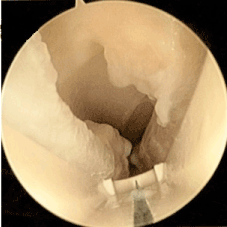

The endoscope should hug the underside of the transverse carpal ligament (TCL) and use the leading edge of the device to push synovium out of the way. Transverse fibers of the ligament should be the only thing visualized in the viewing portal of the device (Figure 3). Defining the distal edge of the TCL is assisted by using a digit from the non-instrument hand to ballot in the area of the distal edge and it is usually 30 mm from the proximal edge of TCL defined at wound dissection. After release (Figure 4) the device is then reinserted to confirm complete division of the transverse carpal ligament.

Figure 3. showing pre-endoscopic release.